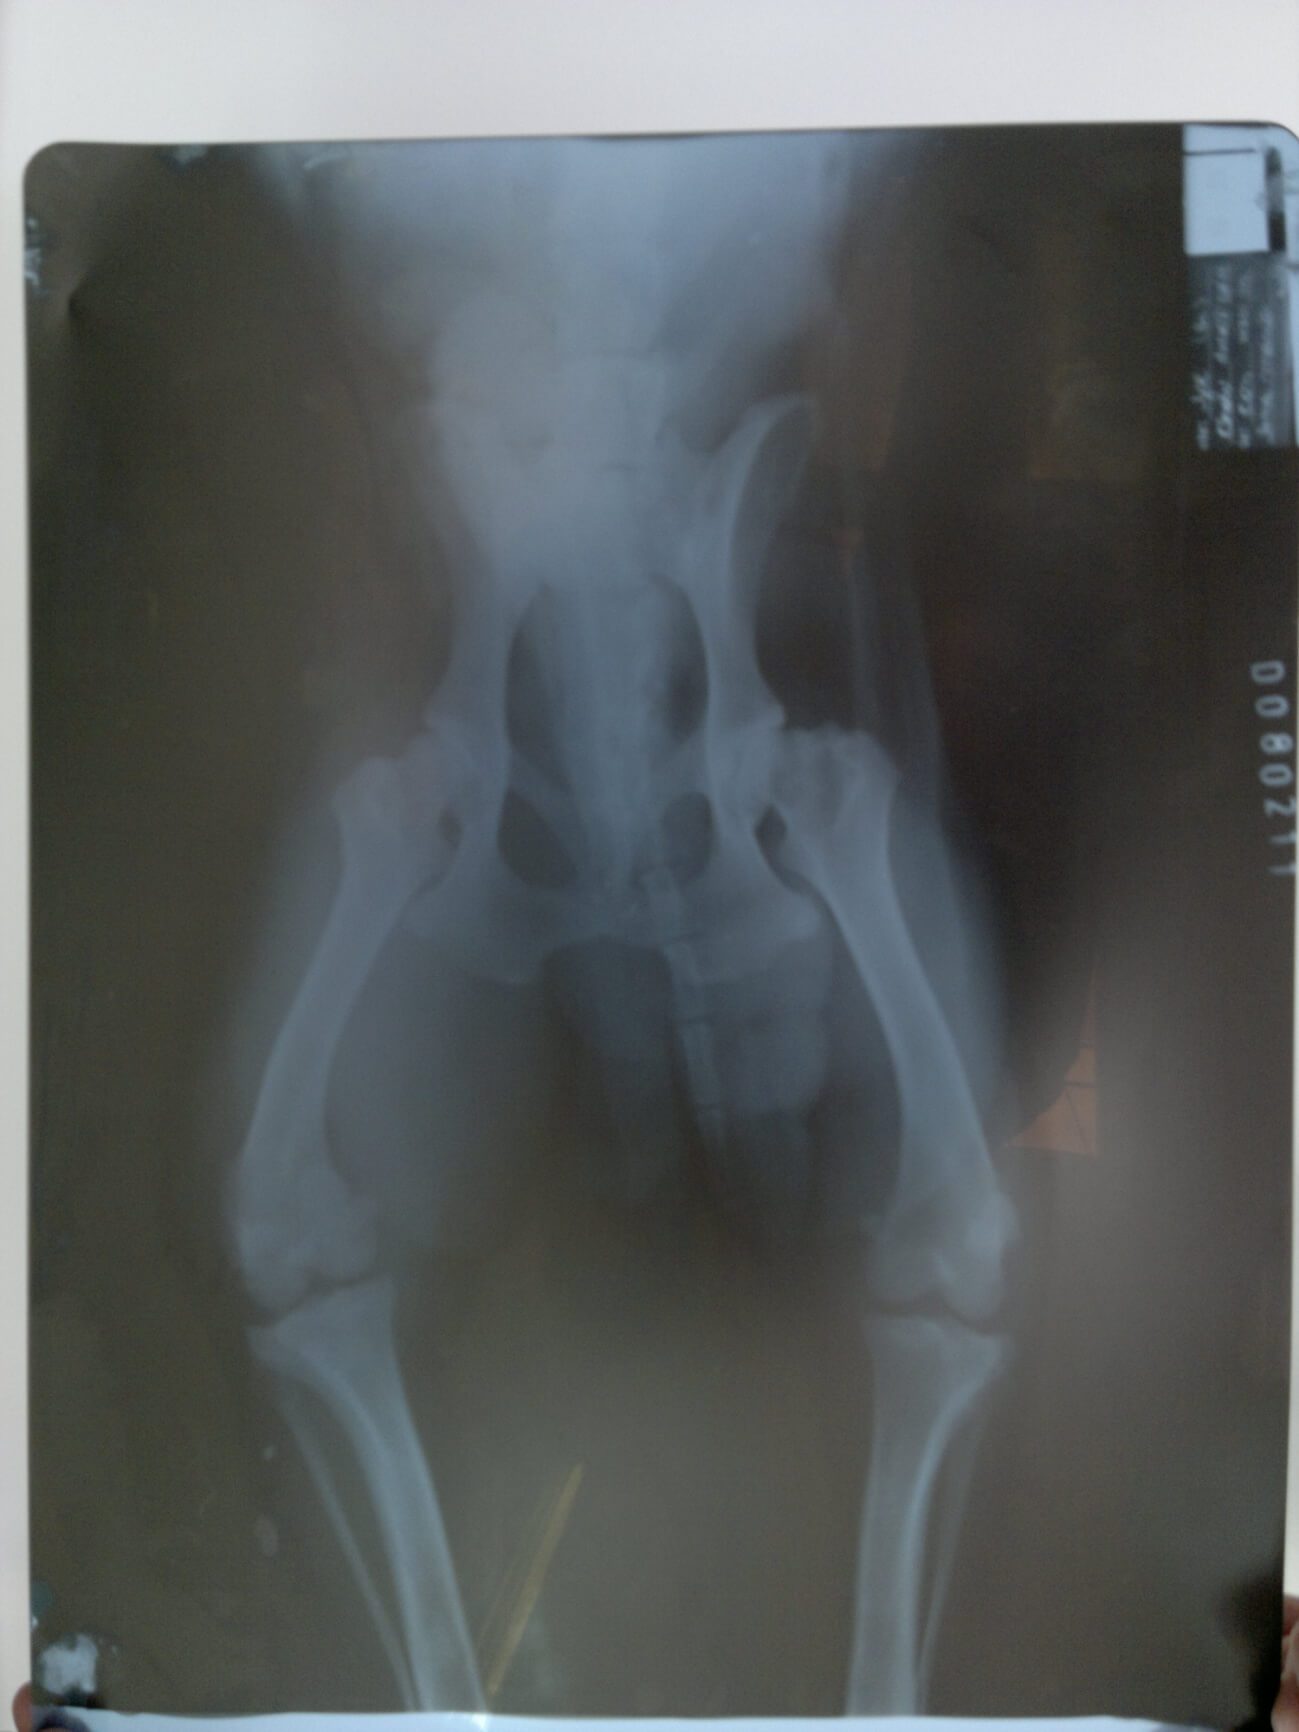

Caso I – Canino, dois anos, macho, raça Lhasa Apso. Claudicava dos membros pélvicos desde jovem. Com cerca de um ano e meio, começou a claudicar também do membro anterior direito. A radiografia (figura 1) revelou Displasia Coxofemoral bilateral grave e Displasia de cotovelo direito. Foi iniciado tratamento com antiinflamatórios e sulfato de condroitina, o animal apresentava melhoras durante o uso do antiinflamatório, mas quando este era suspenso ele voltava a claudicar. Em 21/08/2010 foram suspensos as medicações alopáticas e teve inicio o tratamento com o 1Homeopet Displasia® 2 borrifadas 3 vezes ao dia. A melhora foi progressiva e com apenas dez dias de uso era possível se observar diminuição da claudição. Após 30 dias deste tratamento o animal não apresentava mais sinais de dor e conseguia inclusive subir degraus.

(figura 1)